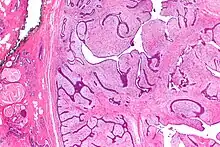

| Micrograph of a phyllodes tumor (right of image) with the characteristic long clefts and myxoid cellular stroma. Normal breast and fibrocystic change are also seen (left of image). H&E stain. |

Phyllodes tumors (from Greek: phullon), are a rare type of biphasic fibroepithelial mass that form from the periductal stromal and epithelial cells of the breast.[1] They account for less than 1% of all breast neoplasms.[2] They were previously termed cystosarcoma phyllodes, coined by Johannes Müller in 1838, before being renamed to phyllodes tumor by the World Health Organization in 2003.[3] Phullon, which means 'leaf' in Greek, describes the unique papillary projections characteristic of phyllodes tumors on histology.[1] Diagnosis is made via a core-needle biopsy and treatment is typically surgical resection with wide margins (>1 cm), due to their propensity to recur.[4]